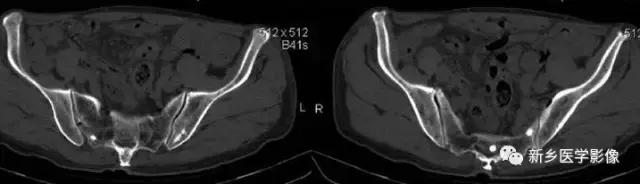

9、输精管钙化

主要表现为盆腔内对称性小钙化灶。